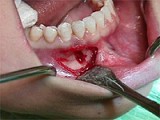

1.組圖是牙齦瘤患者,有關此病的描述不正確的是  (    )

正確答案:D